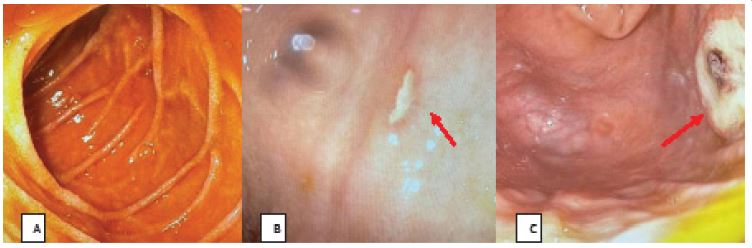

Esophagogastroduodenoscopy (EGD) was performed, as shown in Figures 1 and 2 revealing: stomach lumen filled with bile-stained gastric secretions with intact rugal folds and distensible walls. A wide-based ulcer with heaped-up regular borders and nonbleeding visible vessel at the center, measuring around 3x3 cm, was noted at the fundus. Clean-based ulcers with heaped up regular borders measuring around 1 cm were also noted at the fundus and at the proximal lesser curvature. There were no tortuous vessels seen in the esophagus.

Figure 1: A: Unremarkable Descending Duodenum, B: Clean based ulcer on the corpus, C: Post epinephrine injection and hemoclips application.

Figure 2: D: Gastric Ulcer Forrest Class IIA, E: Ulcer on the Fundus, F: Bile stained gastric fluid.